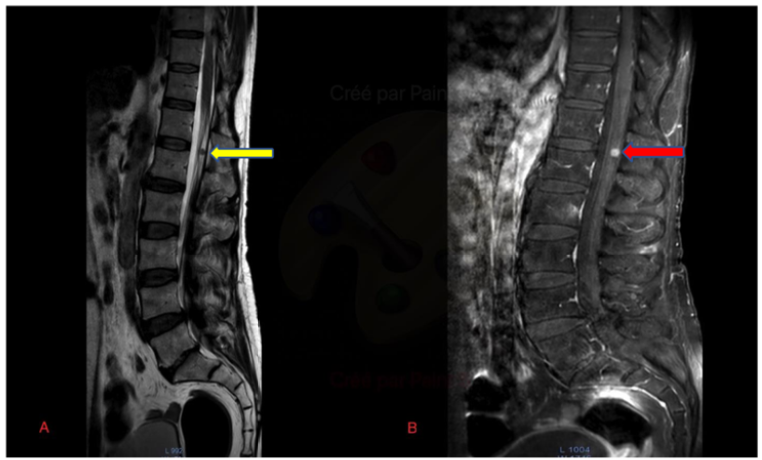

Imaging Utility in the Diagnosis of Dejerine-Sottas Disease: Case Report

Halfi Mohamed Ismail, Zahi Hiba, Fikri Meriem, Jiddane Mohamed and Touarsa Firdaous. 15(5): 88-92.